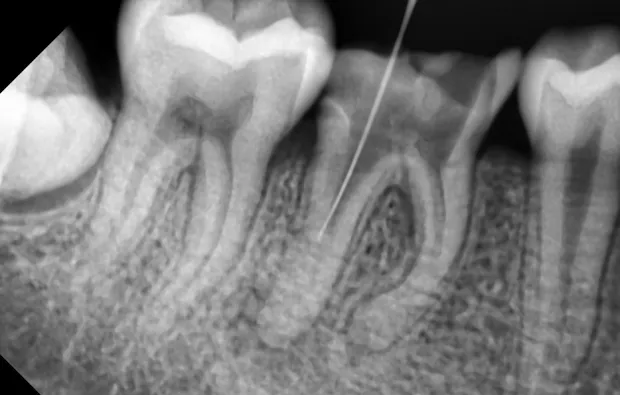

先在断针冠方的根管做通畅的通道。用P钻从最小号逐号进行。一直到准备好的P钻型号。根据手感慢慢的将断针端进入磨好的小洞内,去除断针端1mm左右大部分的牙本质。

再用超声锉去除断针端周围剩余牙本质。然后将超声锉放在断针的侧面震动。以求将断针震松。运气好可以直接震出断针。将小针头慢慢放入根管,顶端的分离处慢慢套入断针,稍稍卡住。再将大针头套入小针头至顶端,慢慢卡紧,最后拔出断针。